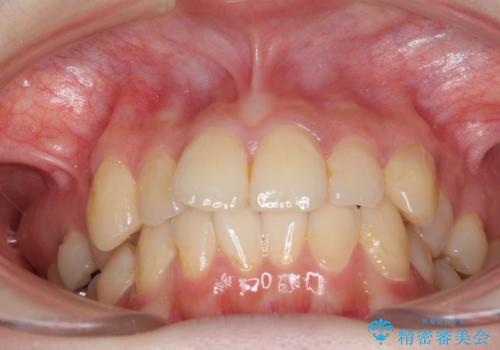

デコボコ歯列をきれいに インビザラインによる矯正治療

- 2年8ヶ月

- 上下歯列全体のデコボコを気にして来院された患者様です。

主に下顎歯列全体の後方移動とIPR(歯と歯の間を削る)によってデコボコが解消するように設計し、インビザラインにより治療を行うこととしました。

奥歯の知覚過敏が顕著となり、その影響で奥歯の咬み合わせ改善のための顎間ゴムの装着ができず、咬合を仕上げるまでに長い期間を要することとなりました。